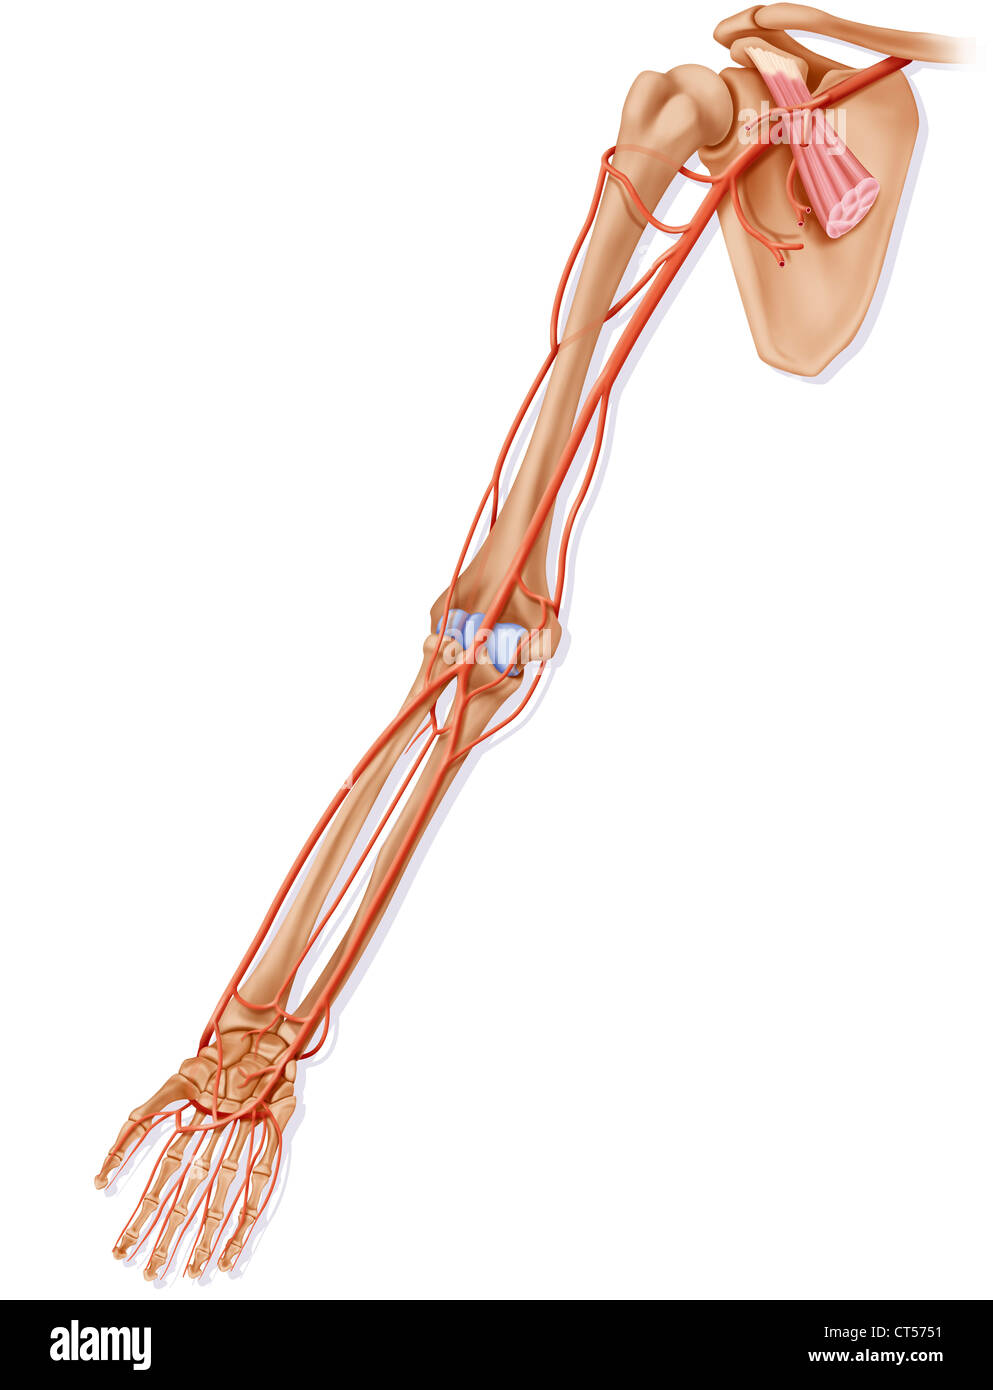

RFEW9HG6–Oberflächlichen Lymphgefäße der oberen Extremität, graviert Vintage Illustration. Üblichen Medizin Wörterbuch - Paul Labarthe - 1885

RFEW91T9–Oberflächlichen Lymphgefäße der oberen Extremität, graviert Vintage Illustration. Üblichen Medizin Wörterbuch - Paul Labarthe - 1885